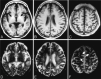

Case 1. AC, Axial T1-weighted MR images obtained 2 days after admission. T1-weighted image (A) shows hyperintensities in the globus pallidus on both sides (arrows). T1-weighted images show no definite signal intensity changes in the cerebral cortices (AC). DF, T2-weighted MR images obtained 2 days after admission. Signal intensity abnormalities are difficult to discern on T2-weighted image (D). T2-weighted images (E and F) show focal, faint hyperintensities in the cerebral cortices (arrows). Confluent and diffuse T2 hyperintensities are seen in the deep and subcortical cerebral white matters (E). G and H, Postmortem axial T2-weighted MR images show deep cortical and subcortical laminar hyperintensities in the entire cerebral hemisphere. Diffuse T2 hypertensities are seen in the deep and subcortical cerebral white matters (G). I and J, Coronal T2-weighted MR images show deep cortical and subcortical laminar hyperintensities in the entire cerebral hemisphere. Hyperintensities are also seen in the deep and subcortical white matters (J). Boxed area in panel I shows hyperintensities in the deep layers of the cerebral cortices and subcortical white matters (open arrows) as well as deep cerebral white matter. The boundary between deep layers of the cerebral cortex and subcortical white matter is not clear. K, The hematoxylin and eosin stained section corresponding to panel J shows laminar pallor of the deep layers of the cerebral cortex (arrowheads) and laminar pallor of the underlying U-fibers (arrows), as well as moderate pallor of the deep cerebral white matter. (Hematoxylin and eosin stain ×100.) L, Histologic findings of the arrowhead area in panel K shows spongy changes of the neuropil, pyknotic, and shrunken neurons (arrowheads) and Alzheimer type II astrocytes (arrows), which have large pale nuclei with marginated chromatin and scanty cytoplasms. (Hematoxylin and eosin stain ×100.) M and N, Histologic findings of the U-fibers (K, arrows) show tissue rarefaction and severe loss of myelin (M) and axons (N). (M, Klüver-Barrera stain ×100; N, Bielschowsky stain ×100.) O and P, Histologic findings of the circled area in panels J and K reveals moderate loss of myelin (O) and axons (P). (O, Klüver-Barrera stain ×100; P, Bielschowsky stain ×100.)